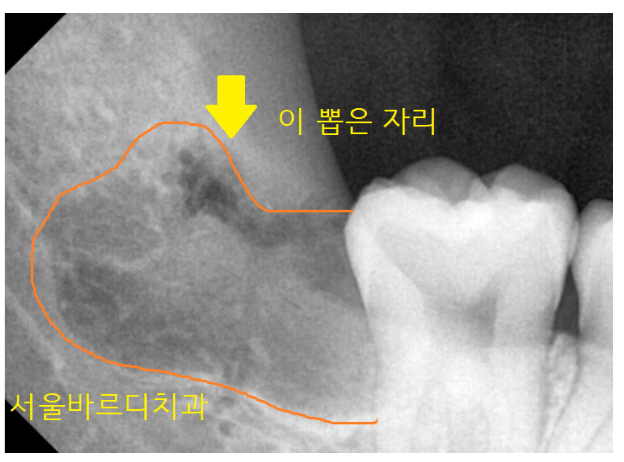

"하치조 신경관"과 겹쳐 있다 보면

뽑고 나서 손상이 있을 수 있는데요.

이때 발생할 수 있는 후유증으로

운동 신경은 아니라 말하고 식사하는 데에는 문제가 없지만...

감각신경이라 입 주변에 느낌이 없을 수 있습니다.

그래서 대학병원 가서 뽑으라고 하는것인데

안전한 발치가 가능할지는 ct를 보면 가능합니다.